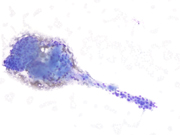

Figure 5: FNA material of the left upper arm lesion, Cell Block, H&E, 200x magnification.

Figure 6: FNA material of the left upper arm lesion, Cell Block, SMA immunohistochemistry, 200x magnification.

The smears (Figures 1-4) show a cellular lesion composed of uniform round-to-oval cells in tight and loose cohesive clusters admixed with strands of magenta-colored material reminiscent of basement membrane. Spindled endothelial cells might be imagined in the periphery or crossing the cell clusters. The cell block material (Figure 5) shows uniformly rounded cells with punched-out nuclei, evenly dispersed nuclear chromatin with inconspicuous nucleoli, and eosinophilic cytoplasm growing around blood vessels. Immunohistochemistry performed on the cell block materials shows that the cells of interest are diffusely positive for SMA (Figure 6), while negative for AE1/3, synaptophysin, chromogranin, S100, and CD31. Ki-67 is very low. The cytologic findings are classic for glomus tumor (GT).

Diagnosis of GT from a FNA specimen can be challenging because the aspirate may be hemorrhagic or paucicellular. The differential diagnosis varies based on the location, often including neuroendocrine tumor, paraganglioma, adnexal tumor in skin, and gastrointestinal stromal tumor in stomach, among others. GTs of all types typically express SMA and MSA. CD34 can be focally positive, but CD31 and ERG are negative in the glomus cells. GTs are negative for neuroendocrine tumor markers and melanocytic markers.